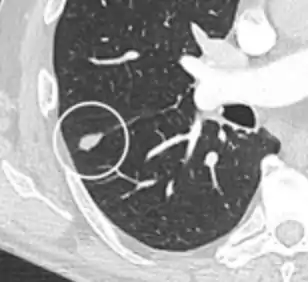

- A lung nodule abutting a pulmonary cyst is a rare finding, yet indicating cancer.[9]

- Bubble-like lucencies in the nodule indicate cancer:[9]

- Vascular convergence is where vessels converge to a nodule without adjoining or contacting the edge of the nodule, and is mainly seen in peripheral subsolid lung cancers.[9] It reflects angiogenesis.[9]